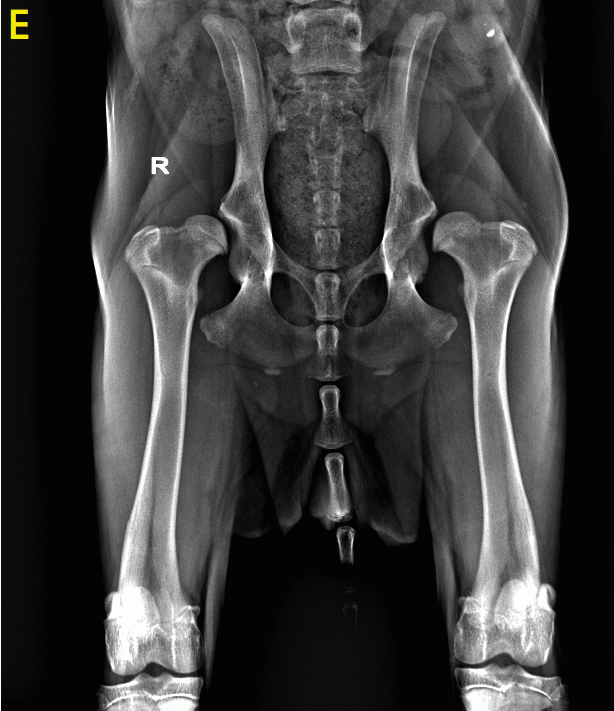

E) displasia dell’anca grave in cucciolo di Golden Retriver di 7 mesi

La displasia dell’anca è una patologia ortopedica non traumatica che colpisce l’articolazione dell’anca durante l’accrescimento. La mancata congruenza tra la testa femorale e la cavità acetabolare determina una grave degenerazione artrosica dell’articolazione compromettendo la qualità di vita e le prestazioni fisiche del cane.

In alcuni cani il problema può essere lieve e comportare poco disagio, mentre in altri casi la displasia puo’ presentarsi in forma più grave, determinando segni clinici rilevanti e/o facendo prevedere seri problemi alla deambulazione sul posteriore in un periodo più tardivo della vita dell’animale.